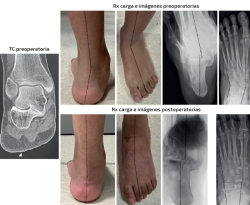

Caso 2 (Figura 5)

Se trata de un paciente varón de 26 años. Clínica de dolor medial y pinzamiento subfibular. Coalición talocalcánea ósea completa. Deformidad en plano, valgo y abducto. Tipo IIB de Myerson. Tratamiento: doble osteotomía del calcáneo (alargamiento de la columna externa + deslizamiento medial) + osteotomía de Cotton. Aloinjerto liofilizado de cresta. Seguimiento: 2,5 años. Mejoría en la alineación clínica y el dolor. Destaca la mejoría en los parámetros radiológicos del retropié tanto dosoplantares como sagitales a pesar de la coalición ósea. Nota: caso cedido por Dr. F. J. Carrillo Piñero).